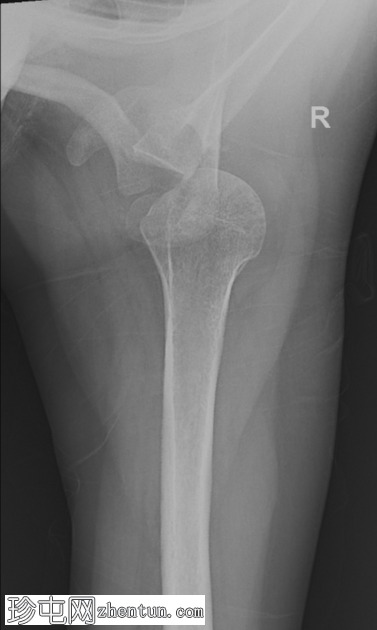

轴位片

肱骨头向后移位至肩胛盂后方,证实肩关节后脱位。现有

未见明确的相关骨折。

轴位片(或肩胛Y形位)对于确认后脱位至关重要。

对于有癫痫发作或触电史的患者,应始终考虑肩关节后脱位的可能性。